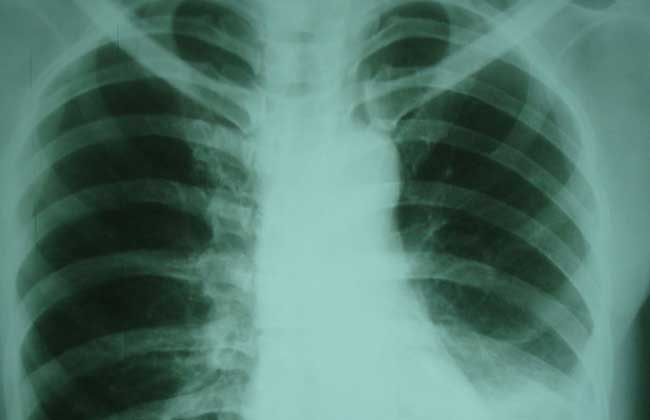

胸膜炎可由肺炎、肺栓塞所致的肺梗死、癌症、结核病、类风湿性关节炎、系统性红斑狼疮、寄生虫感染(如阿米巴病)、胰腺炎、损伤(如肋骨骨折)、由气道或其他部位到达胸膜的刺激物(如石棉)、药物过敏反应(如肼苯哒嗪、普鲁卡因酰胺、异烟肼、苯妥英、氯丙嗪)等引起。